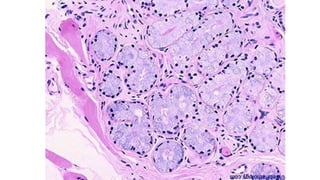

O documento descreve estruturas renais como a macula densa, células de Lacis e glândulas de Littre que fazem parte do aparelho yuxtaglomerular, responsável pela regulação da pressão arterial e do volume de fluidos no corpo.